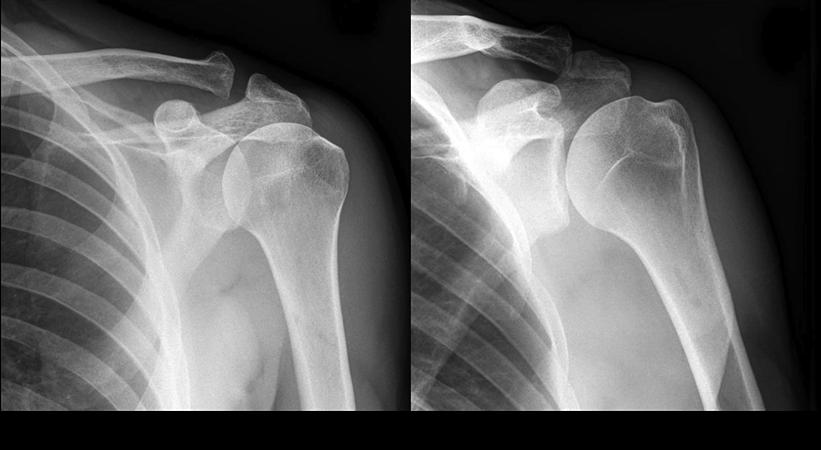

Shoulder hemiarthroplasty is a shoulder replacement in which the damaged humeral head is replaced with a prosthetic humeral head. Shoulder arthroplasty is a rapidly evolving area of orthopedics focused on treating specific, painful ailments of the glenohumeral articulation.

Total Replacement

The standard total shoulder replacement involves replacing the arthritic joint surfaces with a highly polished metal ball attached to a stem, and a plastic socket.

These components come in various sizes. They may be either cemented or press fit into the bone. If the bone is of good quality, we can use a non-cemented (press-fit) humeral component. If the bone is soft, the humeral component may be implanted with bone cement. In most cases, an all-plastic glenoid (socket) component is implanted with bone cement.

Reverse Shoulder Replacement

In a reverse total shoulder replacement, the rounded head of the upper arm bone is removed Using screws and special tools, and a plastic socket is attached to the remaining bone. The socket of the shoulder blade is also removed and is then replaced with a metal ball.